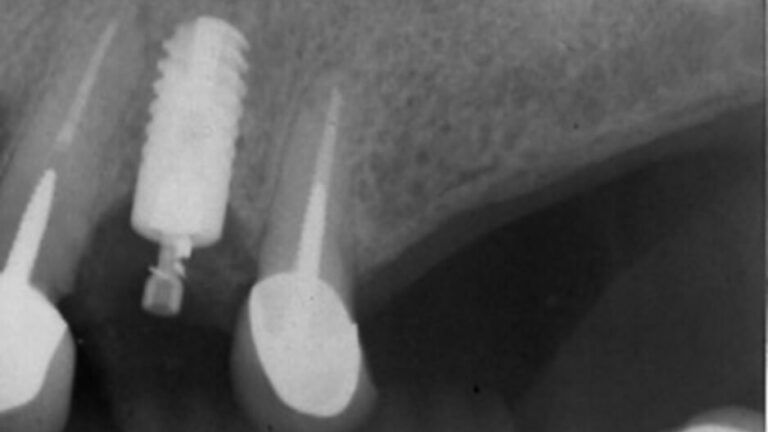

The patient presented on referral from his general dentist with a fractured Ankylos abutment in the #2 site.

The patient presented on referral for retrieval of a fractured zirconia abutment from a Straumann 4.1 BL implant in the #6 site.